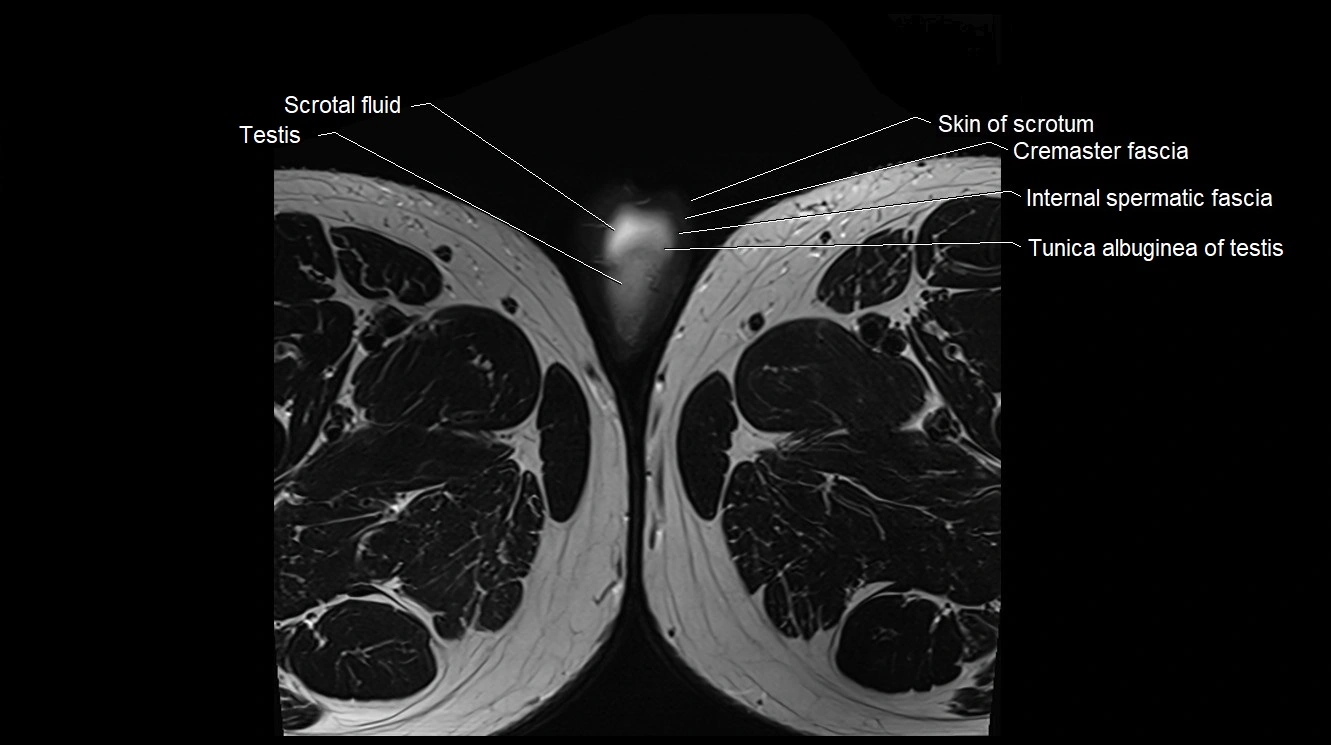

- Cremaster fascia

- Internal spermatic fascia

- Scrotal fluid

- Skin of scrotum

- Testis

- Tunica albuginea of testis